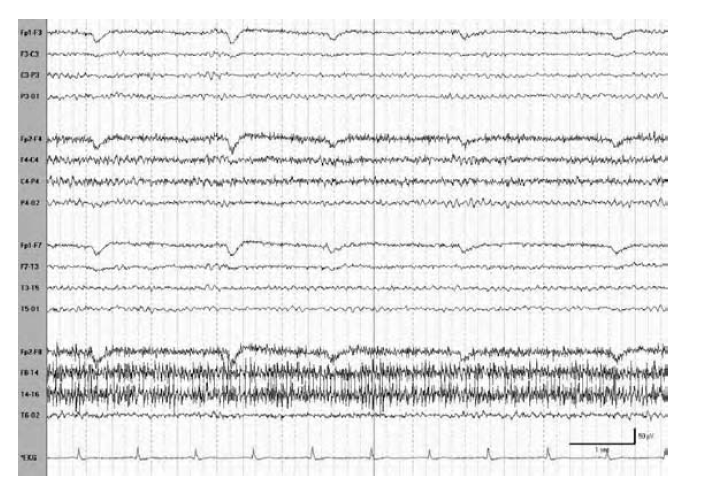

THIS IS AN ARTIFACT. BUT WHAT ABNORMALITY DOES IT MIMIC?

Eye movement monitors confirming a vertical eye flutter artifact with infraorbital electrodes (EOGs) during intermittent photic stimulation (IPS) to differentiate an artifact from frontal intermittent rhythmic delta activity

(FIRDA).